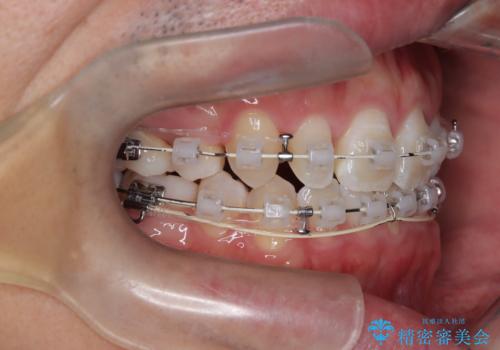

正中の改善と前歯の整列:抜歯を伴う矯正治療の症例

- 前歯のガタガタや正中の不整を改善するために、右上4、左上4、左下4を抜歯し、矯正治療を行いました。この治療により、見た目だけでなく、咬合のバランスも改善され、患者様の口腔内の健康が向上しました。

審美ワイヤー装置は、見た目を重視した矯正治療において非常に有効な選択肢です。患者様のニーズに応じた治療が可能で、美しい歯並びを目指すことができます。